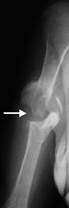

1 2

Рис..42. 1 – полный травматический вывих; 2 – переломовывих.